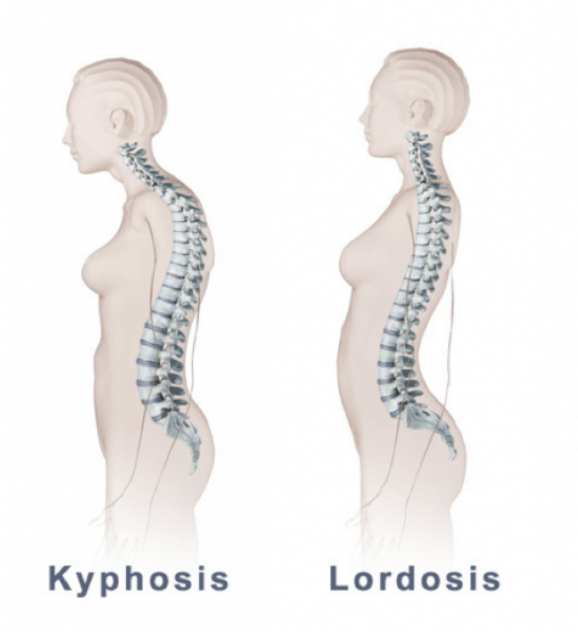

- explain the Kyphosis( hunchback).(કાઇફોસીસને વર્ણવો).

કાયફોસિસ એ સ્પાઇન ની એબનોર્માલીટી છે કે જેમાં સ્પાઇનલ કોડ નું આઉટવર્ડ તરફ કર્વેચર થાય છે.

સ્પાઇનલ કોડૅ એ રાઉંડિંગ ઓર હંચબેક થાય છે.

કાયફોસીસ માં સ્પાઇનલ ની કોન્વેક્સિટી એ આઉટવર્ડ તરફ ઇંક્રીઝ થાય છે.

- explain the Lordosis(લોરડોસિસને વ્યાખ્યાયિત કરો).

લૉર્ડઓસીસ મા લમ્બર સ્પાઇનનું કર્વેચર એ ઇન્વાર્ડ કર્વેચર ઇંક્રીઝ થાય છે. તેથી લૉર્ડોસીસ મા સ્વેબેક(સ્વેબેક:= સ્વેબેક એટલે પેલ્વિક એ આગળની તરફ ટિલ્ટ(ઝૂકવું) થાય છે તથા એબડોમન એ બહાર( પ્રોટ્રુઝન) નીકળી જાય છે)જોવા મળે છે.